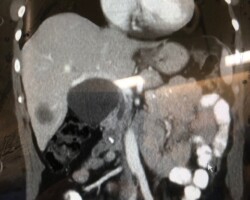

Resection of large retroperitoneal sarcoma including right and transverse colectomy and right hepatectomy